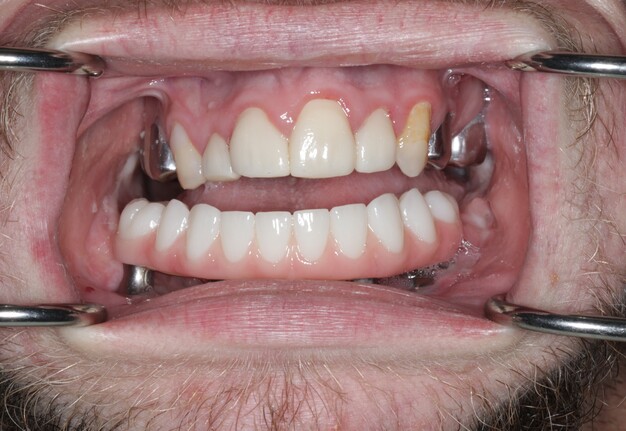

5. Final Prosthesis

The refined prototype was rescanned on the back-pour cast, and a definitive monolithic implant supported fixed zirconia prosthesis was fabricated and successfully delivered (Figs 16 and 17).

Verification of passive seating, which could not be performed radiographically due to the inability to fit x-ray films intraorally, was carried out by visual confirmation on the fabricated physical cast followed by intraoral verification. The full arch implant supported fixed prosthesis was fully seated with no rocking or movement. A high-water design was utilized for enhanced hygiene, eliminating the need for tissue capturing and moulage. Passiveness was verified visually and tactically using a new sharp probe, with no evident gap. A one-screw test was performed to ensure there was no elevation on the opposite end. A screw resistance test was also performed, with all Vortex screws hand-tightened due to the inability to insert a torque wrench intraorally.

The prosthesis was fabricated from multilayered 3Y/5Y zirconia (Ivoclar Vivadent), directly milled without metal Ti-bases, and sealed with Teflon and resin composite. Occlusal contacts were checked, fine refinements were made, and the restoration was polished prior to final insertion.